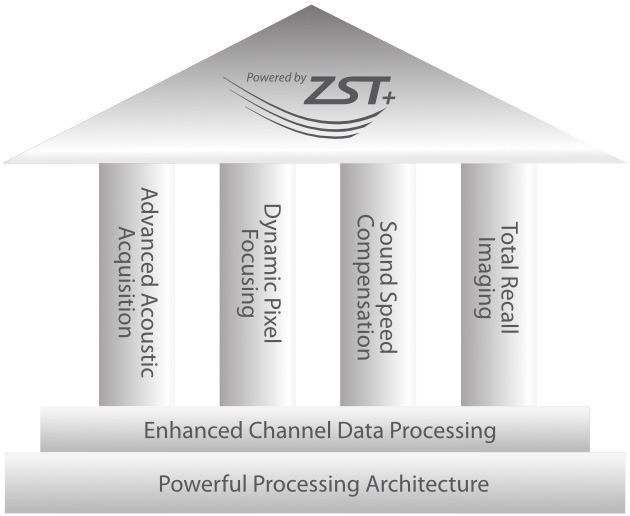

Powered by ZST +

Für die Ultraschalltechnologie stellt die ZST+-Plattform einen bedeutenden Fortschritt dar, da sie statt der herkömmlichen Strahlformung die Kanaldatenverarbeitung verwendet. Diese bahnbrechende Innovation löst übliche Zielkonflikte zwischen räumlicher Auflösung, zeitlicher Auflösung und Homogenität des Gewebes auf, woraus sich eine beispiellose Bildqualität ergibt, die den Weg frei macht für unendlich viele Bildgebungslösungen.